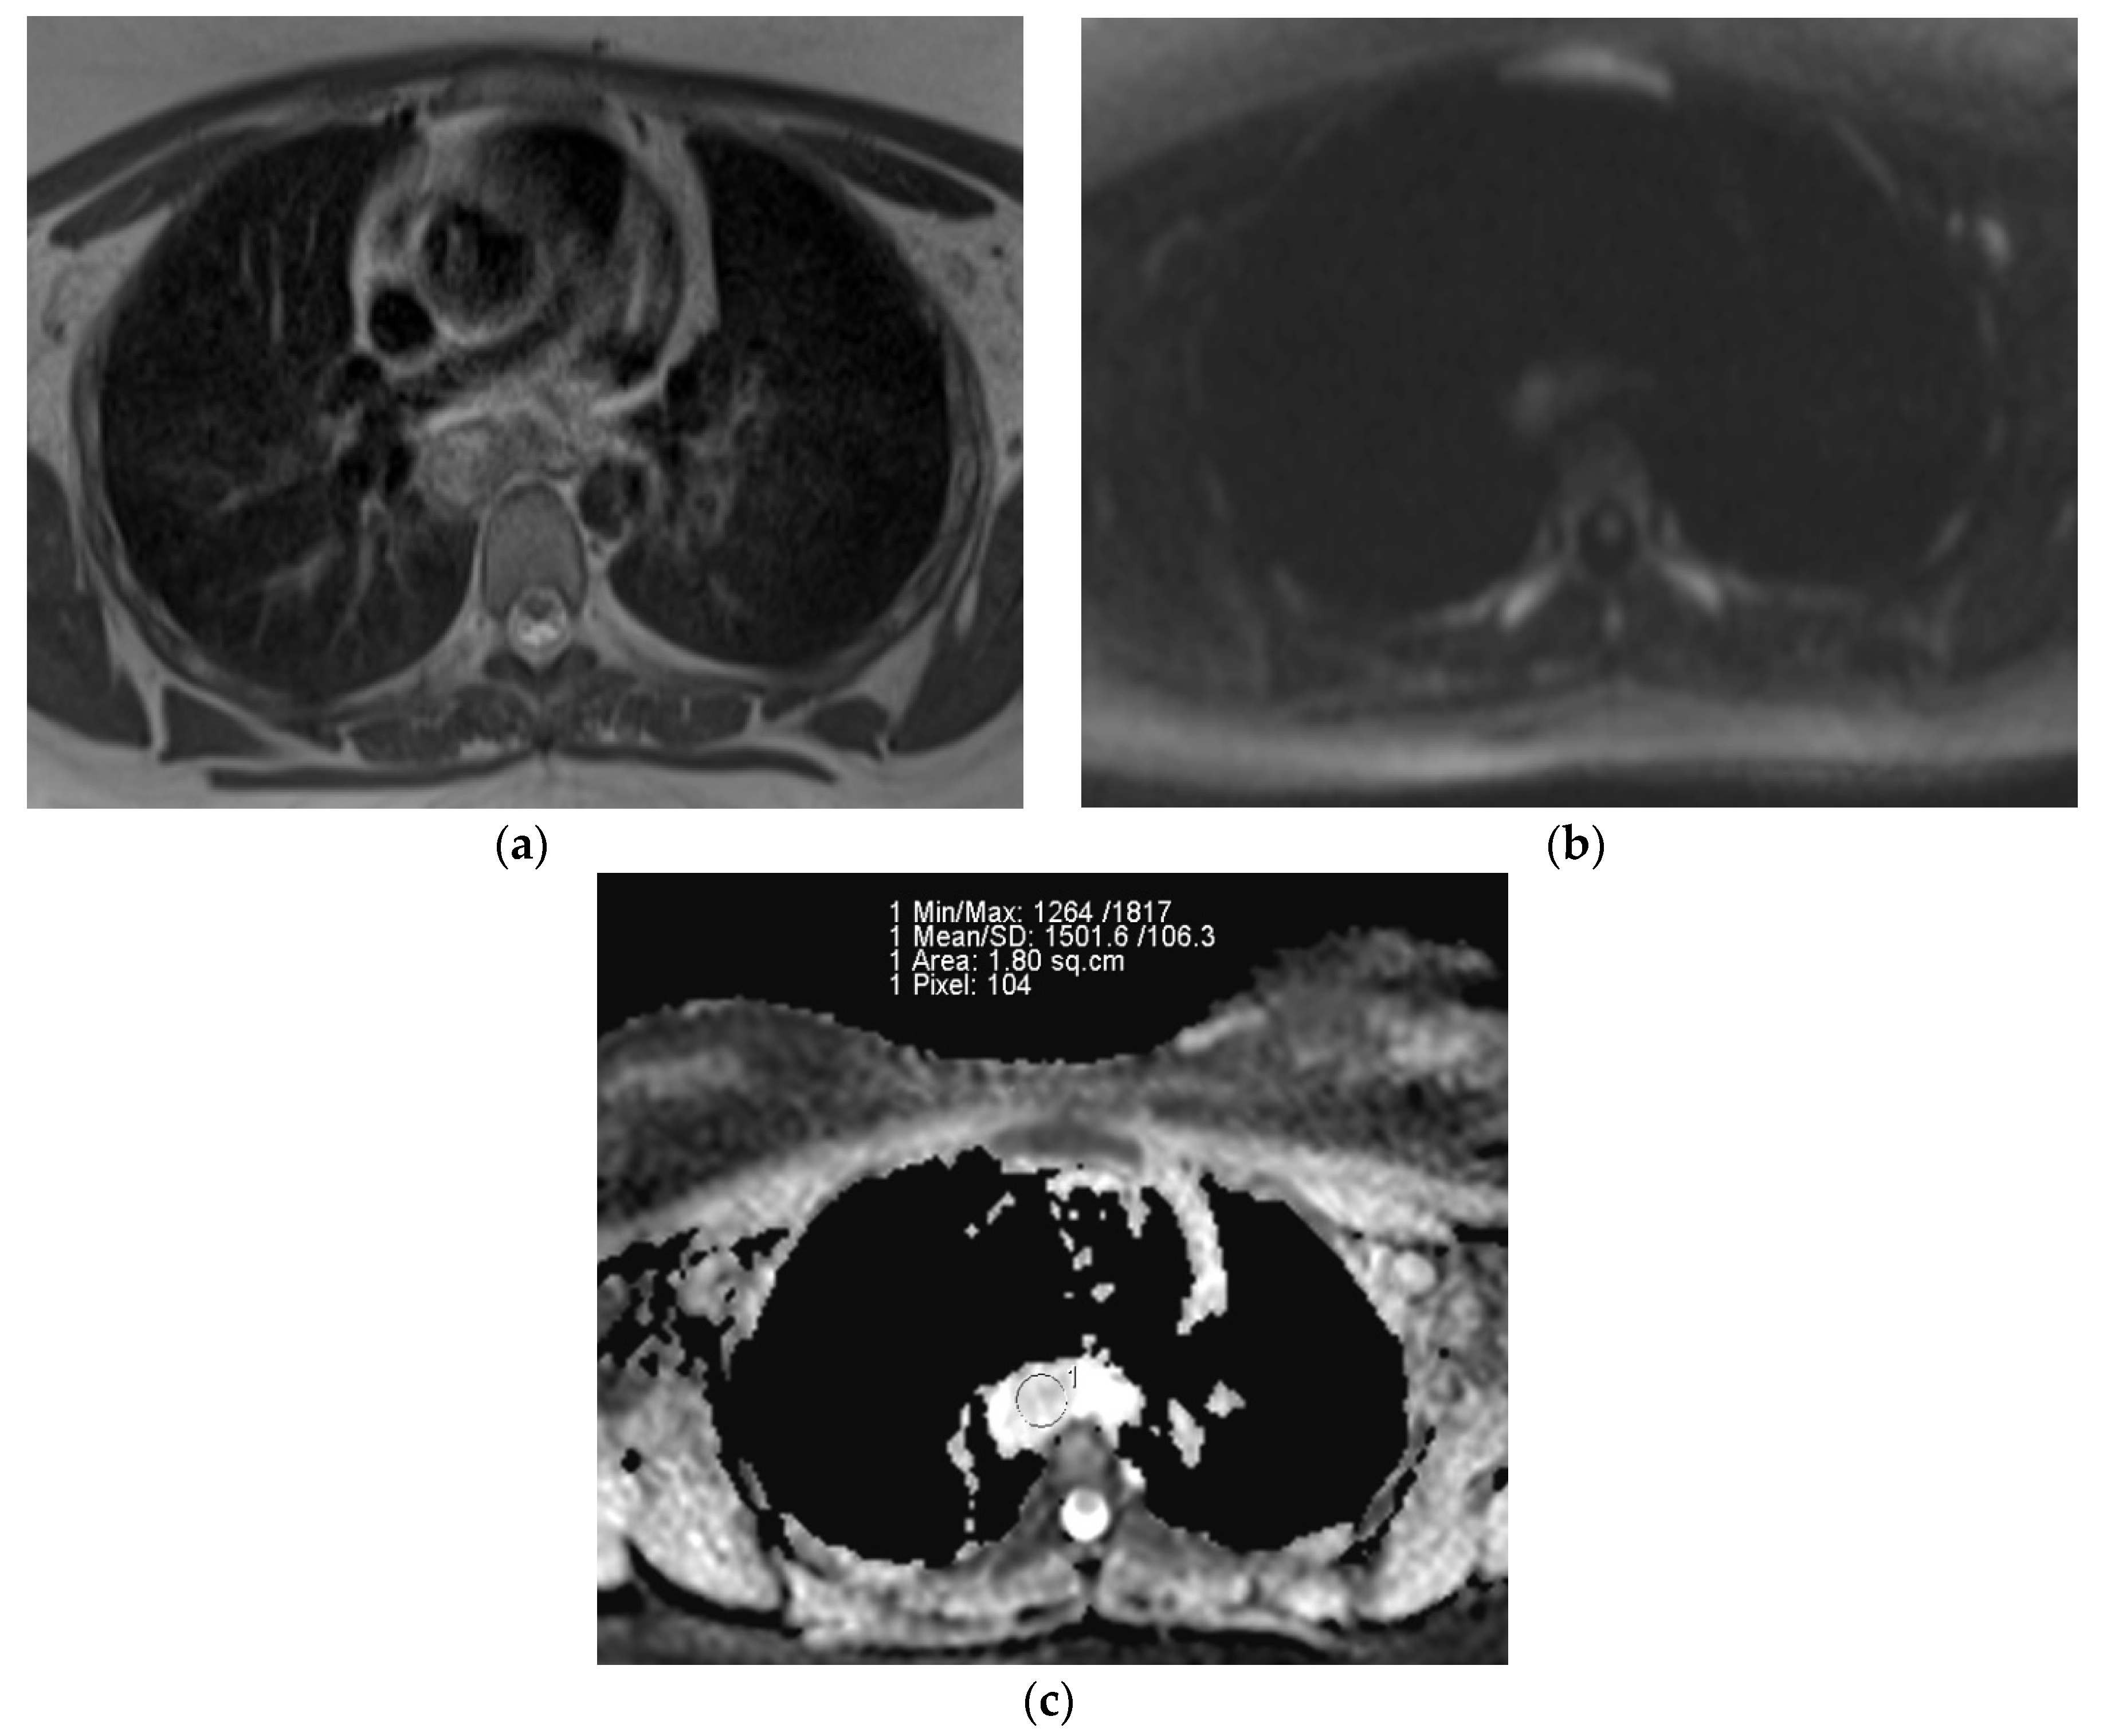

There was a significant difference between the ADC of malignant lymph nodes (0.873 ± 0.109 × 10−3 mm2/s) and benign lymph nodes (1.663 ± 0.311 × 10−3 mm2/s) (p = 0.001). The difference in distribution of ADC values of benign and malignant lymph nodes is depicted in a box and whisker plot (Figure 4). ROC curve analysis also revealed that an ADC cut-off value of 1.095 × 10−3 mm2/s could differentiate between benign and malignant lymph nodes with 94% sensitivity, 96% specificity, and an AUC of 0.996 (Figure 5).

Figure 5.

ROC curve of ADC values to differentiate malignant and benign lymphadenopathy. (AUC = 0.996; SE = 0.006; asymptotic significance < 0.001; 95% confidence interval 0–1.0). ROC; receiver operating characteristic, AUC; area under the curve, SE; standard error.